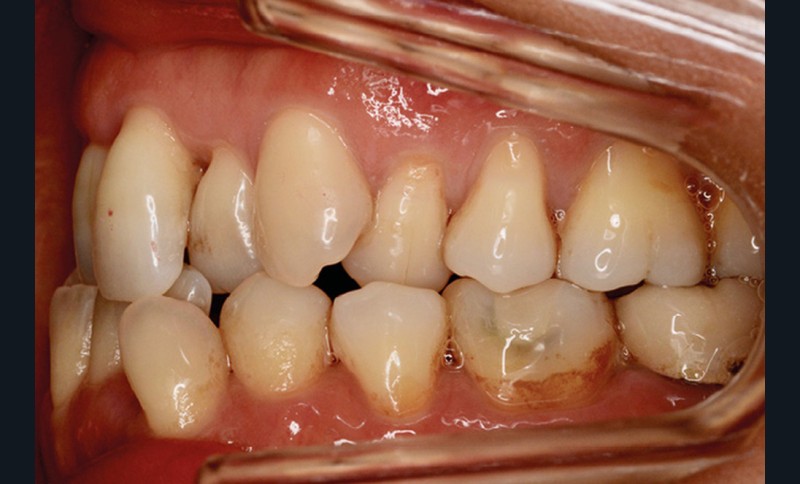

Présentation du cas (fig. 1 à 9)

Sur le plan squelettique, on retrouve une classe III de Ballard par hypomaxillie, dans un schéma facial hyperdivergent.

Sur le plan dentaire, la patiente est en classe III droite et gauche, canine et molaire de 6 mm, avec une occlusion inversée antérieure localisée à 11, 12 et 22. Elle présente une dysharmonie dents-arcades sévère, une agénésie d’une incisive mandibulaire est à signaler, et les troisièmes molaires ont été extraites à l’âge de 21 ans.

Au niveau fonctionnel, on note un bruxisme statique avec contact permanent entre les dents maxillaires et mandibulaires. La patiente présente des prématurités en relation centrée sur les incisives, le guidage en propulsion est perturbé et des interférences multiples sont retrouvées en latéralités droite et gauche.